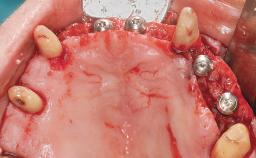

Immediate Loading of Eight Implants in the Maxilla and Six Implants in the Mandible and Final Restoration with Three-Unit and Four-Unit FDPs

Extensive scientific evidence has confirmed that immediately loaded implants with fixed full-arch provisional restorations can osseointegrate with success rates similar to conventionally or delayed loaded implants. A number of immediate-provisionalization techniques for edentulous jaws have been described. Some protocols differ when it comes to prefabricated provisional templates versus complete denture conversion; intrasurgical impressions versus direct relining; and cemented versus screw-retained provisional restorations. In this context, complete-denture conversion has been proposed for either intrasurgical impressions or direct relining. Another possibility is the utilization of a prefabricated provisional to be adapted either in the mouth (by direct relining) or in the laboratory (on a working model obtained from an intrasurgical impression).

Defining Characteristics Fully edentulous upper jaw to be rehabilitated with four or more implants

Modality 6+ implants with immediate loading